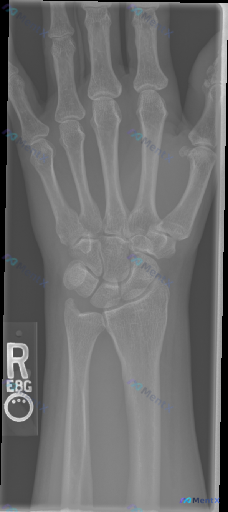

整理到一份右手及腕关节正位X光片的影像分析资料,分享给大家一起讨论。 影像观察到的关键信息: - 骨骼完整性:桡骨远端、腕骨序列、掌骨及指骨未见明确皮质断裂;但在尺骨茎突部位可见明显的皮质不连续,有一条透亮的骨折线,骨折块有轻微分离移位。 - 关节间隙与对合:桡腕关节、腕中关节及腕掌关节间隙清晰,腕...